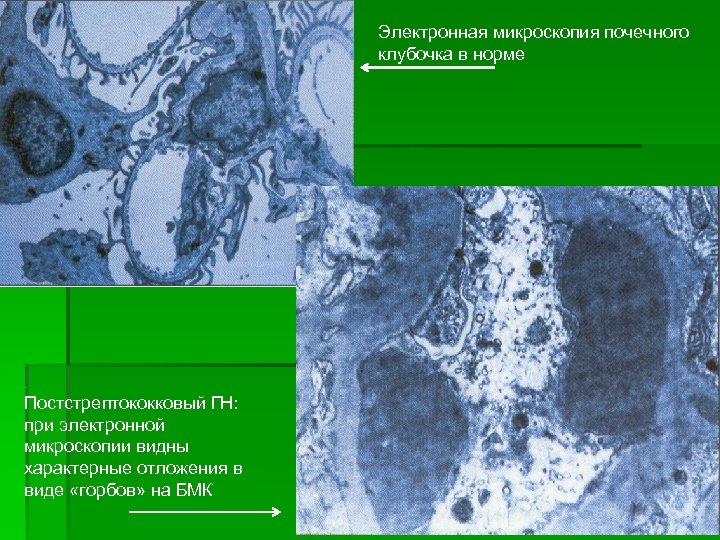

Электронная микроскопия почечного клубочка в норме Постстрептококковый ГН: при электронной микроскопии видны характерные отложения в виде «горбов» на БМК